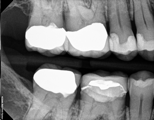

Conventional Endodontic Treatment/Retreatment with Prefabricated Bonded Post and Core

Conventional Endodontic Treatment with Minimal Clinical Crown: Cast Post and Core Coronal Restoration